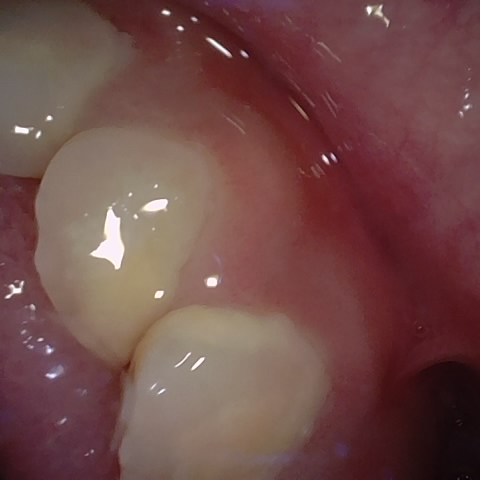

Annotated as "Good"

Original Image Rendering Image